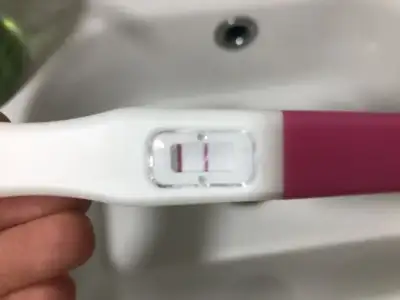

özel hastaneye giderseniz nöbetçi her zaman var çok yüksek değil 90 TL ye yapıyorlar. siz bilirsiniz tabiakşam heyecandan uyuyamadım sabaha karşı dalmışım, sabah işe bile geç kaldım normalde erkenden gidip kan verecektim normalde. Akşam da 17de kapatıyormuş ben 17:30 da işten çıkıyprum kaldı pazartesiye